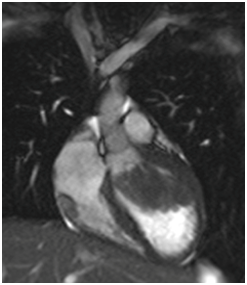

All images are acquired in classical cardiac plans and specific plans over the mass (Figure 1-3).

Figure 1 Left Ventricular out tract flow of cine True FISP SSFP sequence showed intracavitary left ventricular mass sessil, mobile, with obstructive effect over left ventricular out tract blood flow (long arrow); and right ventricular intramiocardial small mass adjacent to atrioventricular sulcus with involvement of tricuspid annulus (short arrow).